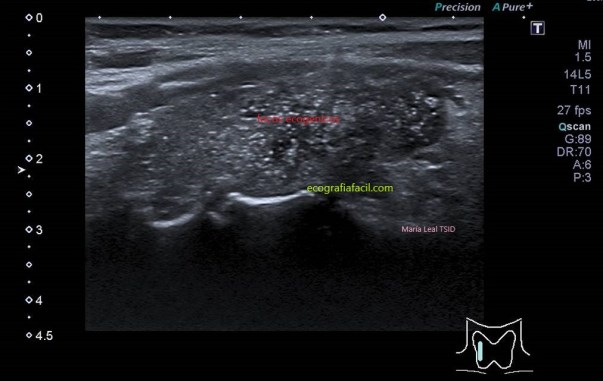

TI-RADS 5

Alta sospecha de malignidad (mayor del 80%)

COMPOSICIÓN: Sólida                           2

ECOGENICIDAD: Muy hipoecoica          3

FORMA: Más largo que ancho               3

MARGEN: Irregular                                 2

FOCOS ECOGÉNICOS: (puntiformes)       3

13 puntos